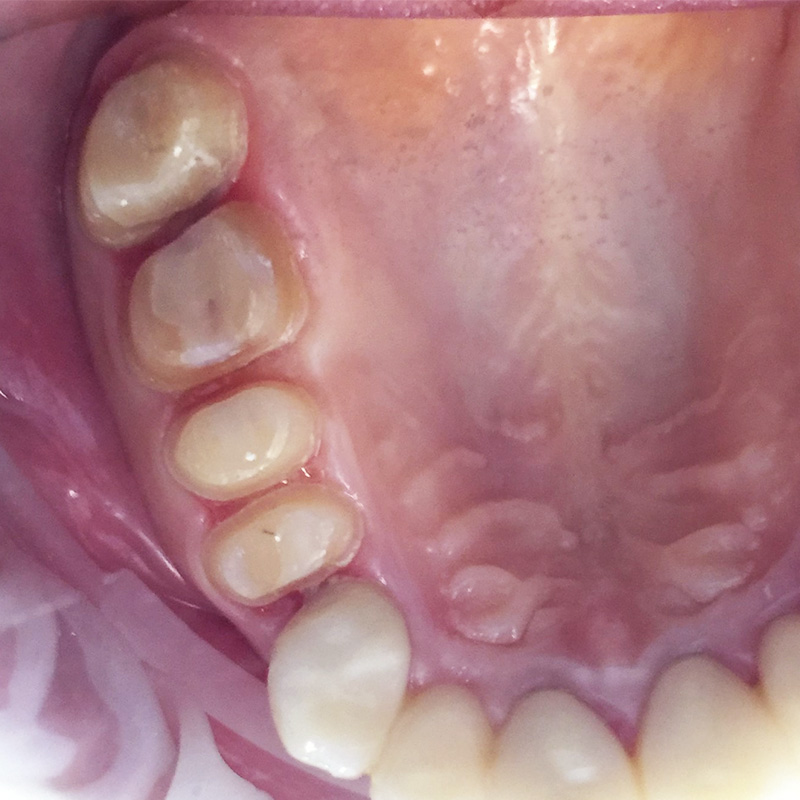

До и после лечения

В нашу клинику обратилась пациентка с целью восстановления эстетики зубов на верхней челюсти.

В ходе лечения были проведены следующие работы:

- профессиональная гигиена полости рта;

- препарирование эмали зубов;

- снятие слепков;

- изготовление и установка цельнокерамических коронок на 15-17 зубы.